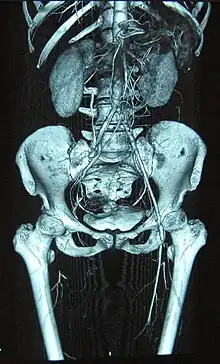

Complete occlusion of the right and stenosis of the left femoral artery as seen in a case of thromboangiitis obliterans | |

Angiograms of the upper and lower extremities can be helpful in making the diagnosis of Buerger's disease. In the proper clinical setting, certain angiographic findings are diagnostic of Buerger's. These findings include a "corkscrew" appearance of arteries that result from vascular damage, particularly the arteries in the region of the wrists and ankles. Collateral circulation gives "tree root" or "spider leg" appearance.[1] Angiograms may also show occlusions (blockages) or stenosis (narrowings) in multiple areas of both the arms and legs. Distal plethysmography also yields useful information about circulatory status in digits. To rule out other forms of vasculitis (by excluding involvement of vascular regions atypical for Buerger's), it is sometimes necessary to perform angiograms of other body regions (e.g., a mesenteric angiogram).